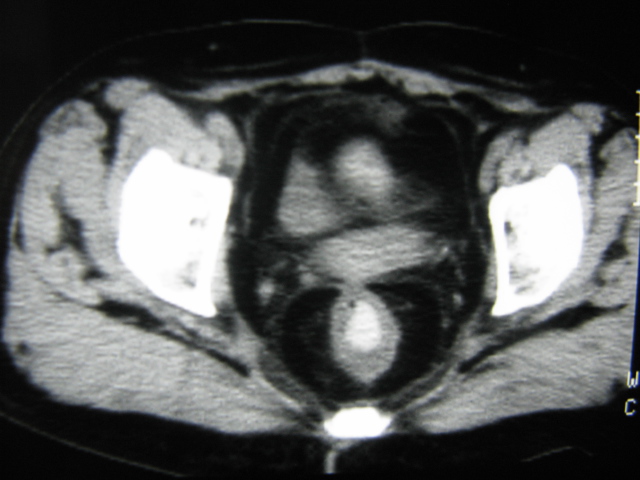

患者,女,64岁,2002年诊断为宫颈癌,当时只做过放,化疗。现在诊断:(1)宫颈癌。(2)直肠癌。请同道们讨论,探讨。另外肠壁为啥密度这么高,ct值约112hu。患者没有做过增强和造影。

高密度的不是肠管影,是肠管内的粪便影

患者直肠病变,排便不畅,粪便硬结造成,更高密度如钡灌肠者都可出现

硬结粪便能有如此高密度影?

患者是否长期服用抗癌药物?应与服用药物有关!

是否与放、化疗有关?

我也碰到过几例,最离奇的一例是全结肠呈造影样高密度,患者直肠癌(首次发现),以往没有吃药,只有约半年时间长的胃纳差,排便不畅(据患者说每次大便只能拉出少许黄水)

不一定有意义,可清洁灌肠后复查